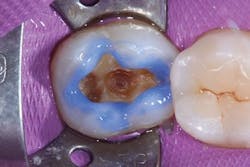

The selective etching technique was chosen, and 37% phosphoric acid (Total Etch, Ivoclar Vivadent) was applied for 30 seconds. The tooth was irrigated with water spray and air-dried (figure 2). Next, a universal bonding agent (Adhese Universal, Ivoclar Vivadent) was scrubbed on the cavity surface until an immobile layer was achieved (figure 3). The excess solvent was removed with an air stream for 20 seconds, and the adhesive was light cured for 10 seconds with an LED light (Bluephase Style, Ivoclar Vivadent) 1 mm away from the cavity.